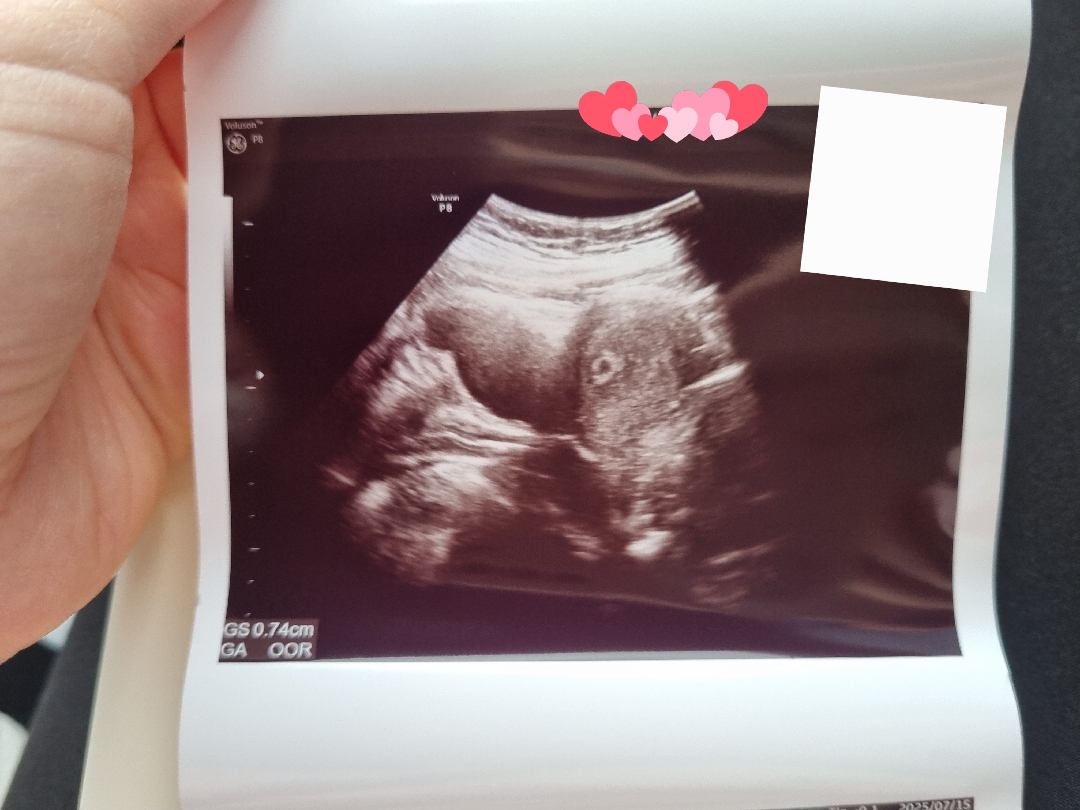

아직 심장소리 듣기 전이어서 출산예정일은 바뀔수 있다고 하셨어요! 저도 말띠맘이 되었네요ㅎㅎㅎ 모두모두 행복하게 태교하시구 건강하게 순산하세요~

감사합니다~ 4주 후반에 보고, 오늘은 5주에요^^